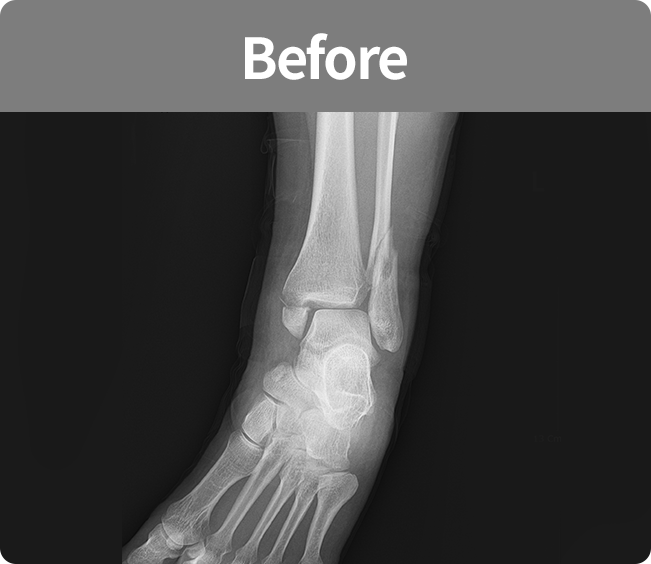

골절 고정술

부러진 뼈를 해부학적 위치로 정확하게 맞춘 뒤,

뼈가 안정적으로 붙을 수 있도록 금속판, 나사, 핀 등을 이용해 고정하는 수술

(내고정술, 외고정술)